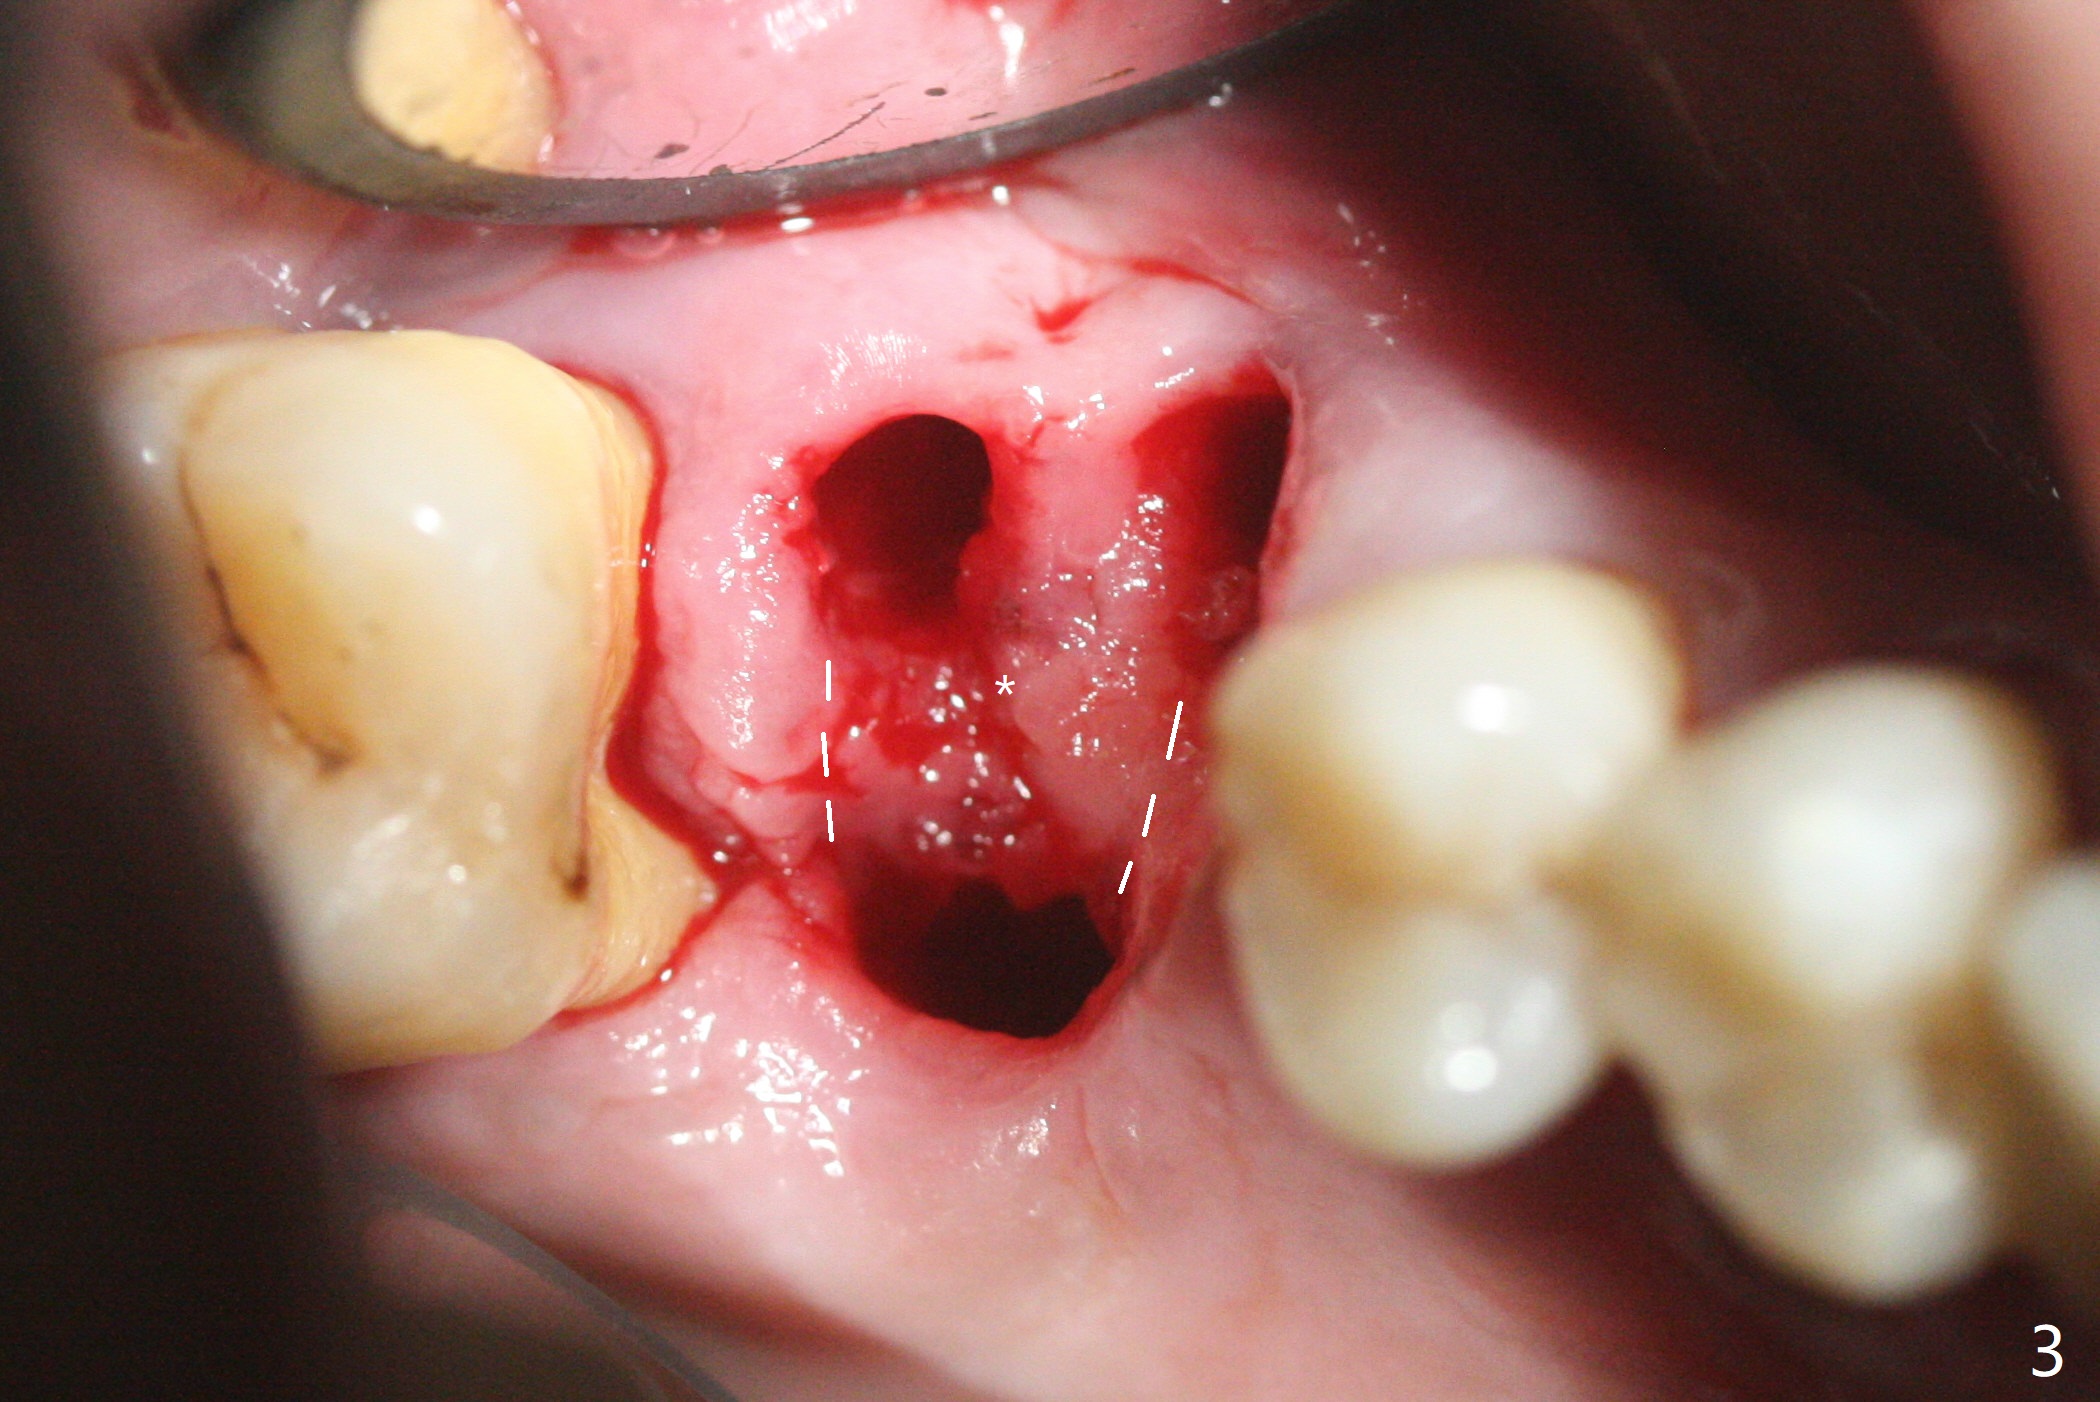

53岁男吸烟,牙周炎,咬合力大,3号牙颊侧(图一),腭侧(图二:P)牙龈退缩,尤其是近中颊侧根(图一:MB),拔牙后,中隔冠方(表面)有好像健康的牙龈(图三:*),近中,远中连接处切开(图三:虚线),将中隔牙龈推向近中颊侧牙槽窝(图四:箭头),修复退缩牙龈,而且暴露下面中隔(S),接着在它上面导板钻洞,避免软组织创伤。利用报废植体试图内提升(图五(红虚线:窦底)),最终正式植体完成提升(图六:黑*),初步在牙槽窝深部放置粘性骨粉(白*)后,放入基台,之后再次在植体,基台周围放置骨粉(图七:*),最后借助临时牙冠(图八,九:T)和外衬里(图八:R)封闭牙槽窝开口,G是近中颊侧迁移的牙龈。植体垂直进入上颌窦可以减少窦膜破裂(图五,六,九),术后没有鼻出血。术后1个月临时牙冠松动,去除牙冠和基台,安置愈合帽(图十)。表面骨粉遗失,但是颊侧移位的中隔牙龈好像帮助软组织预后。